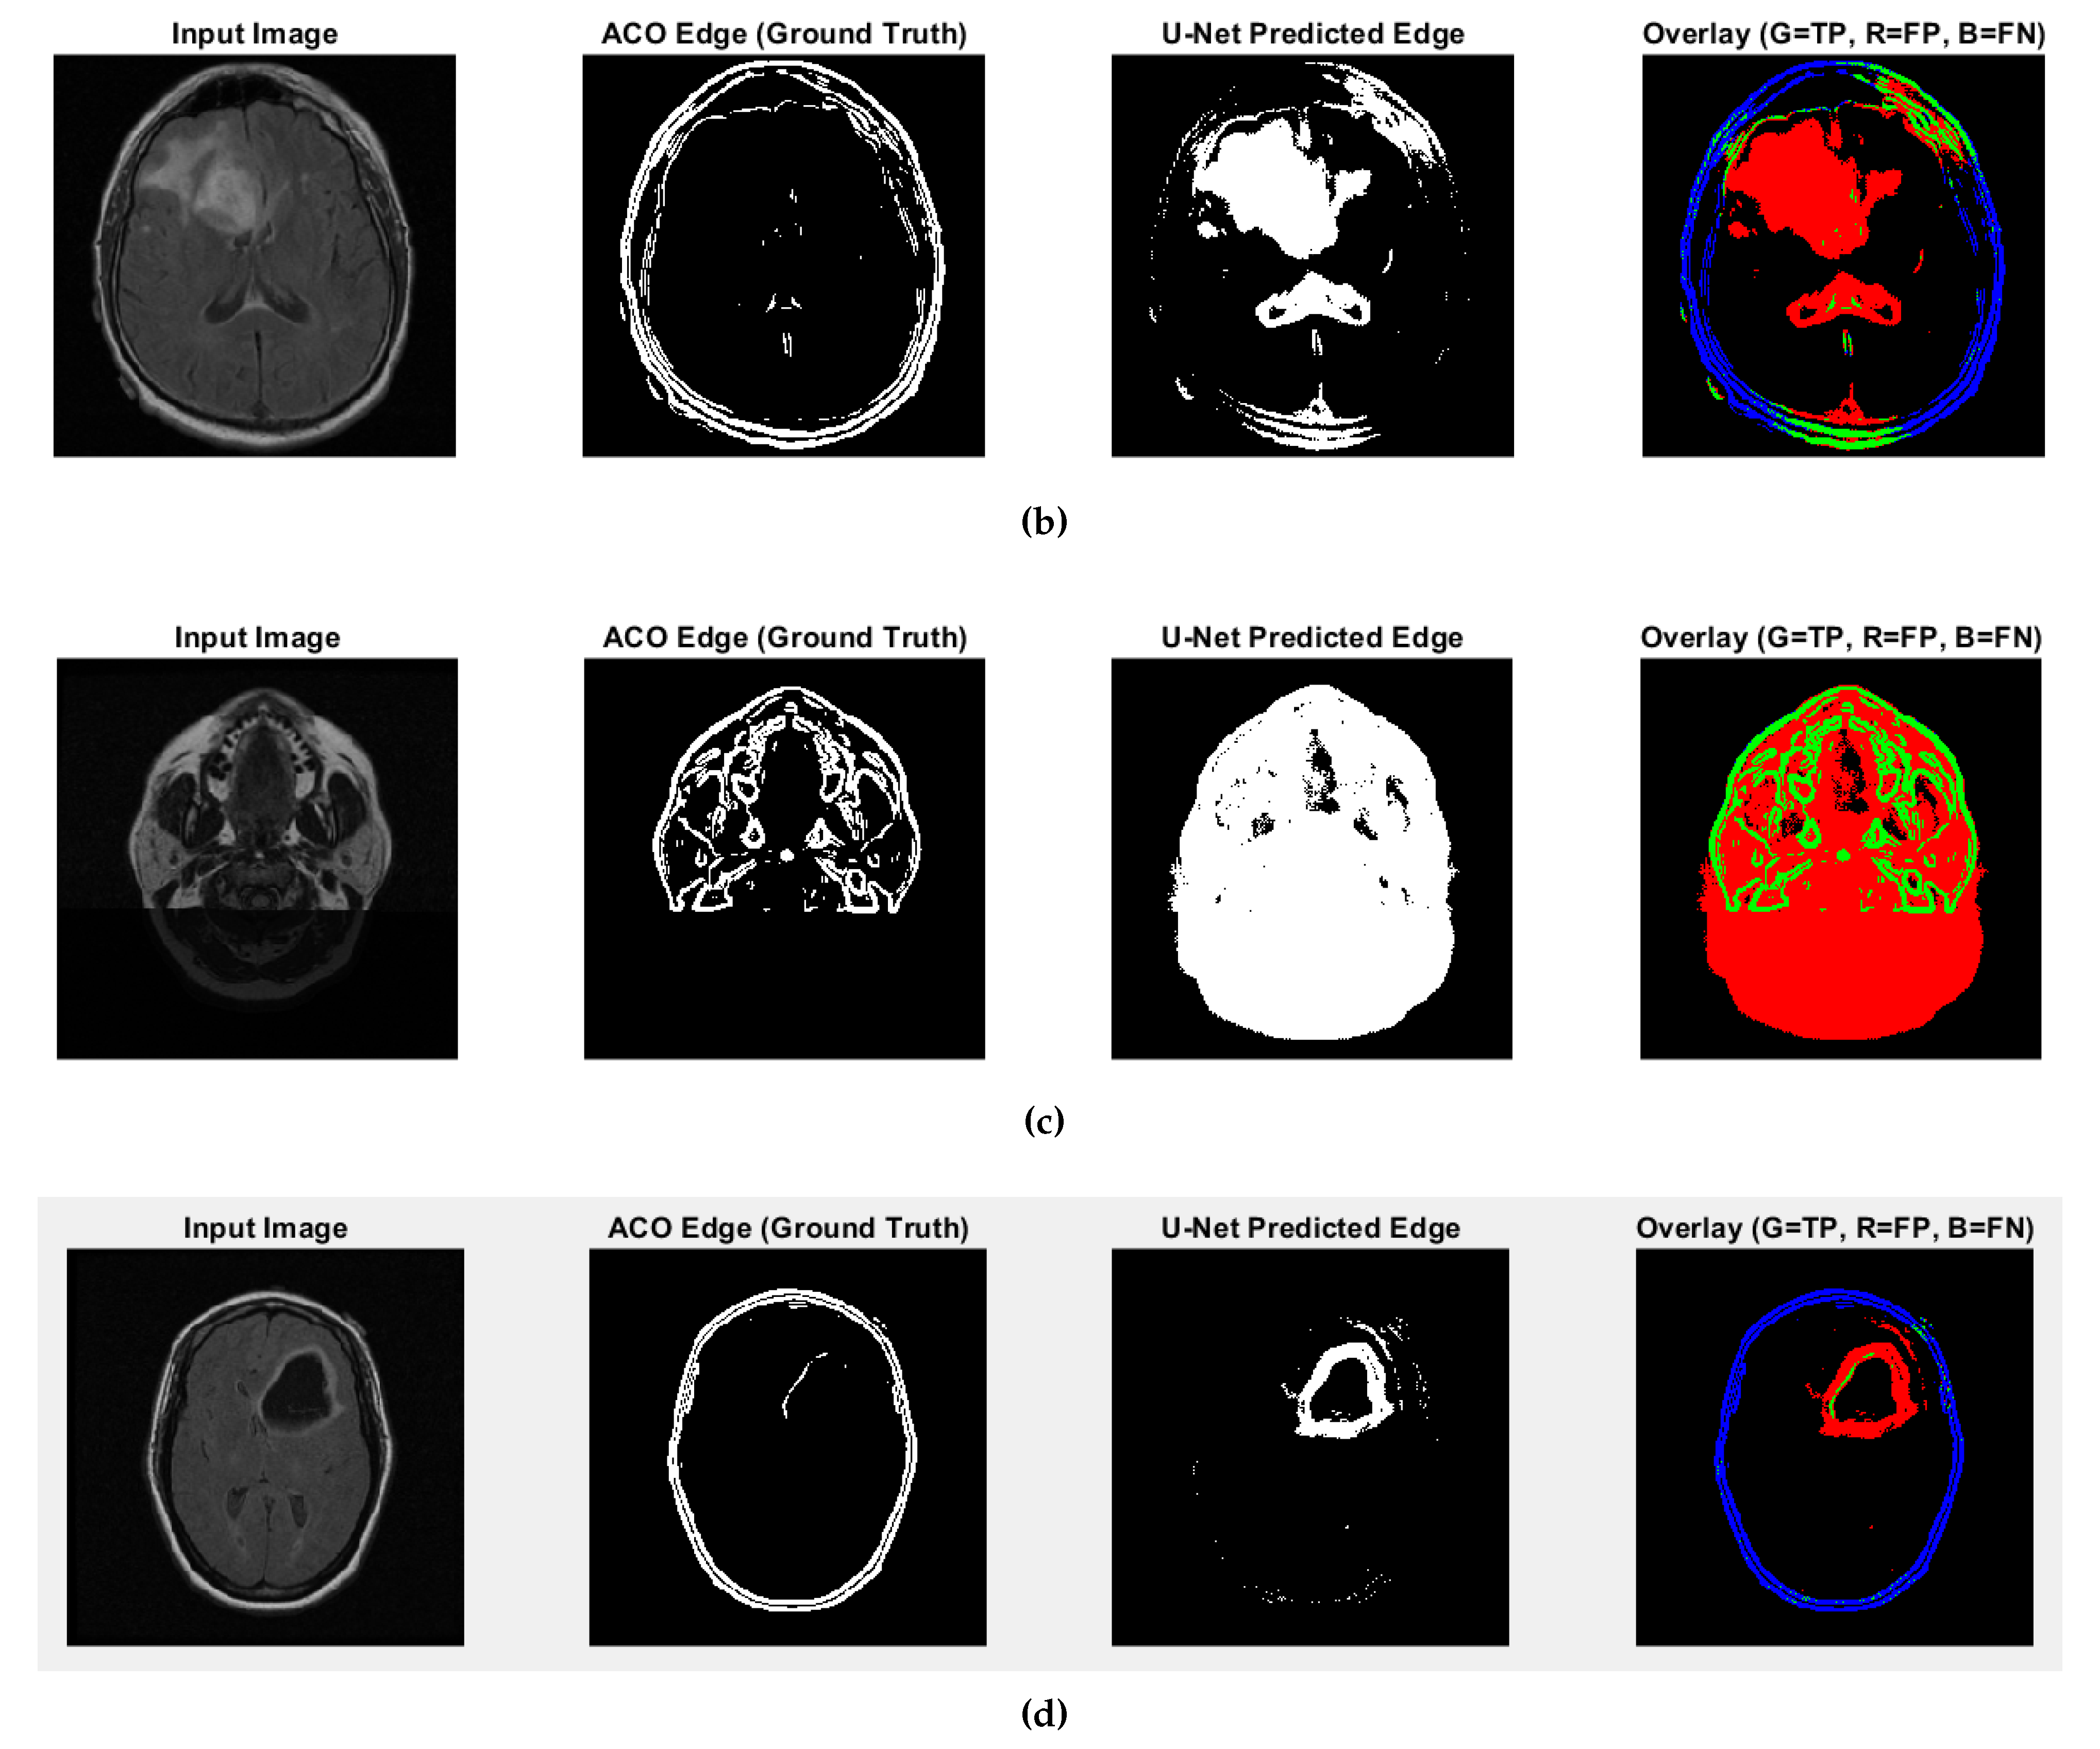

Additional Tests: U-Net and Numerical Comparison with ACO

- High recall values (e.g., 0.9880 and 0.9963 for CS1 and DU1 images) indicate that in these cases, the model successfully identified most ground truth edge pixels—though often with excessive prediction (over-segmentation);

- Very low recall (e.g., 0.0483 for DU2 image) shows that in some cases, the model fails to detect most of the true edge pixels—under-segmentation;

- Low precision values across all cases (from 0.0952 to 0.2342) suggest that many of the predicted edge pixels do not match the ground truth, indicating high false positive rates;

- F1-score and Jaccard Index are low overall (F1 from 0.0641 to 0.3786; Jaccard from 0.0331 to 0.2335), pointing to a general mismatch between predicted and true edge locations;

- SSIM and Max NCC vary from moderate to low (SSIM up to 0.7892, NCC mostly below 0.33), reflecting inconsistent structural similarity and limited pixel-level correlation across cases.